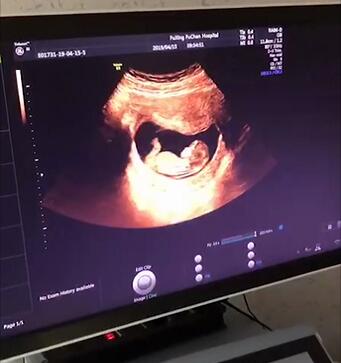

怀孕11—13周+6天

这个时候胎儿基本上已稳定,需要去医院建档,并且进行NT检查。

NT检查,又称颈后透明带扫描,是通过B超手段测量胎儿颈项部皮下无回声透明层较厚的部位,用于评估胎儿是否有可能患有唐氏综合征的一种方法,能检测胎儿的生长发育情况、胎盘环境、子宫状况等,是十分重要的检查,孕妈们不可掉以轻心。

Q: 疫情防控期间,能否推迟做NT检查的时间?

NT的变化与孕周密切相关,严格规定测量其厚度的时间为孕11-13w+6天。当孕14周后,过多的液体可能被胎儿正在发育的淋巴系统吸收,检查结果就会不准确。所以想要做NT检查的孕妈们要掌握好检查的时间哦~